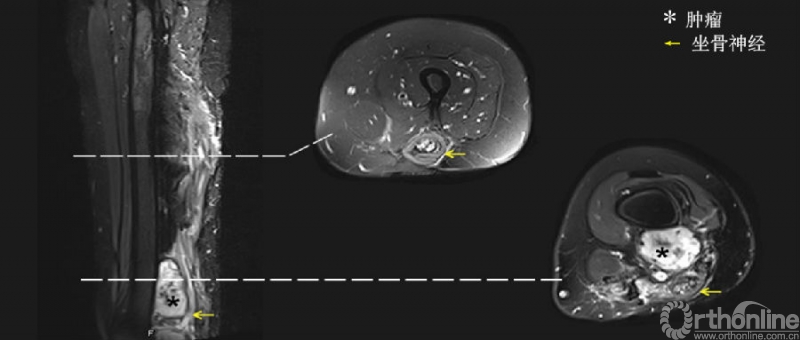

术前磁共振提示肿瘤包绕坐骨神经与腘血管。周围肌肉组织行广泛切除,坐骨神经与腘血管R2切除后行三明治隔离手术,术后55.5月随访过程中,补片隔离区域未见复发。

术后磁共振影像提示隔离区域无复发,而非隔离区域内有病变进展